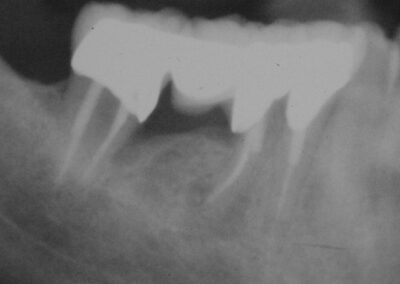

Aufgrund der linken Aufnahme könnte man fälschlicherweise vermuten, dass die mesiale Wurzel des hemisezierten 6ers erneut oder nach wie vor beherdet ist. Wie man jedoch auf dem rechten Zahnfilm eindeutig erkennt, handelt es sich lediglich um den (noch?) nicht vollständig remineralisierten engen Bereich der ehemaligen Aufhellung um die Wurzel, der in seiner knöchernen Struktur mit derjenigen der ehemaligen Extraktionswunde der distalen Wurzel vergleichbar ist.

Beachtenswert ist insbesondere der „wundersame Knochengewinn“ im Bereich der mesialen Wurzel von 47 und interdental 45/46 im Vergleich zum Ausgangsbefund. Sehr deutlich wird auch die Reduktion der Parodontalspalten in der Folge der Eliminierung der Entzündung und der schützenden Ruhigstellung durch die primäre Verblockung